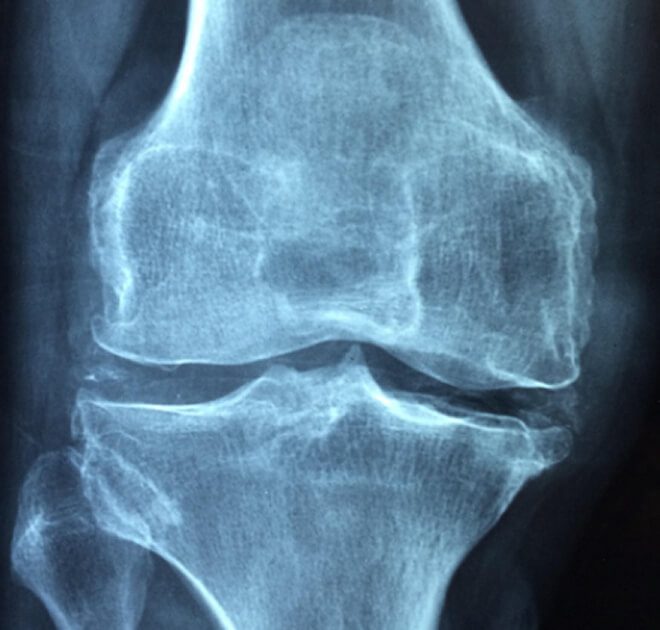

Accidents involving heavy equipment, machinery, or vehicles can result in traumatic knee injuries, including fractures, dislocations, and ligament tears. These injuries may require immediate medical attention and extended recovery.

A knee injury generally refers to a traumatic incident or condition caused by a specific event, such as a fall or a direct blow to the knee. A knee strain, on the other hand, typically refers to the overuse or overstretching of muscles or tendons, often caused by repetitive movements. Both types of injuries can qualify for workers’ compensation if they are linked to job duties.